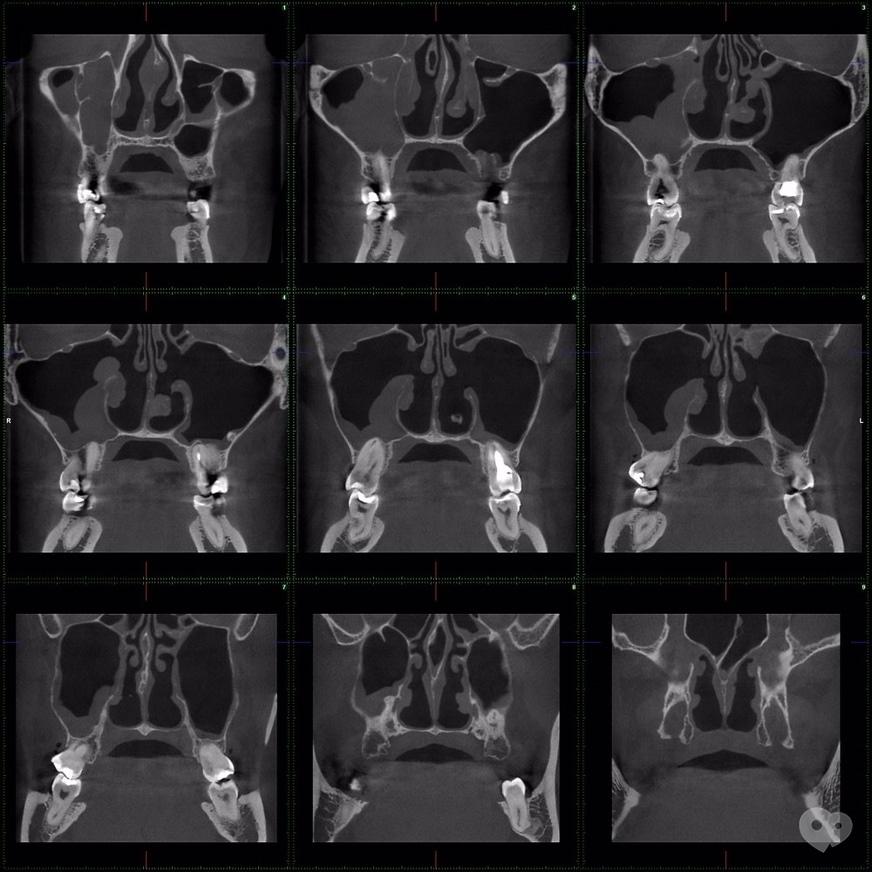

Обследование ппн

Обследование ппн 118 фото